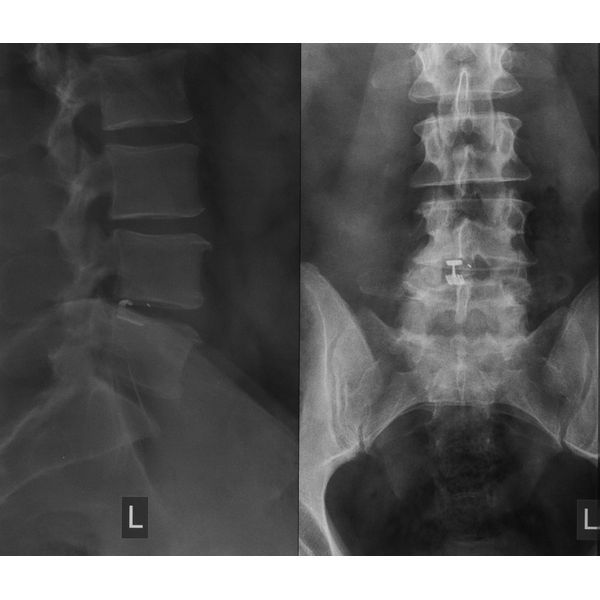

Магнитно-резонансная томография (МРТ) поясничного отдела позвоночника выявила:

- большую парамедианно-латеральную грыжу диска L4–L5, т. е. она была расположена слева от центра и направлена вбок;

- сдавление (компрессия) левого корешка L5;

- признаки разрыва фиброзного кольца (наружной оболочки диска);

- выраженное поражение диска (IV стадия по классификации Pfirrmann).

Остеохондроз поясничного отдела позвоночника. Грыжа межпозвонкового диска L4–L5 слева с компрессией корешка L5. Радикулопатия. Секвестрация диска (пульпозное ядро отделилось от диска). Разрыв фиброзного кольца.